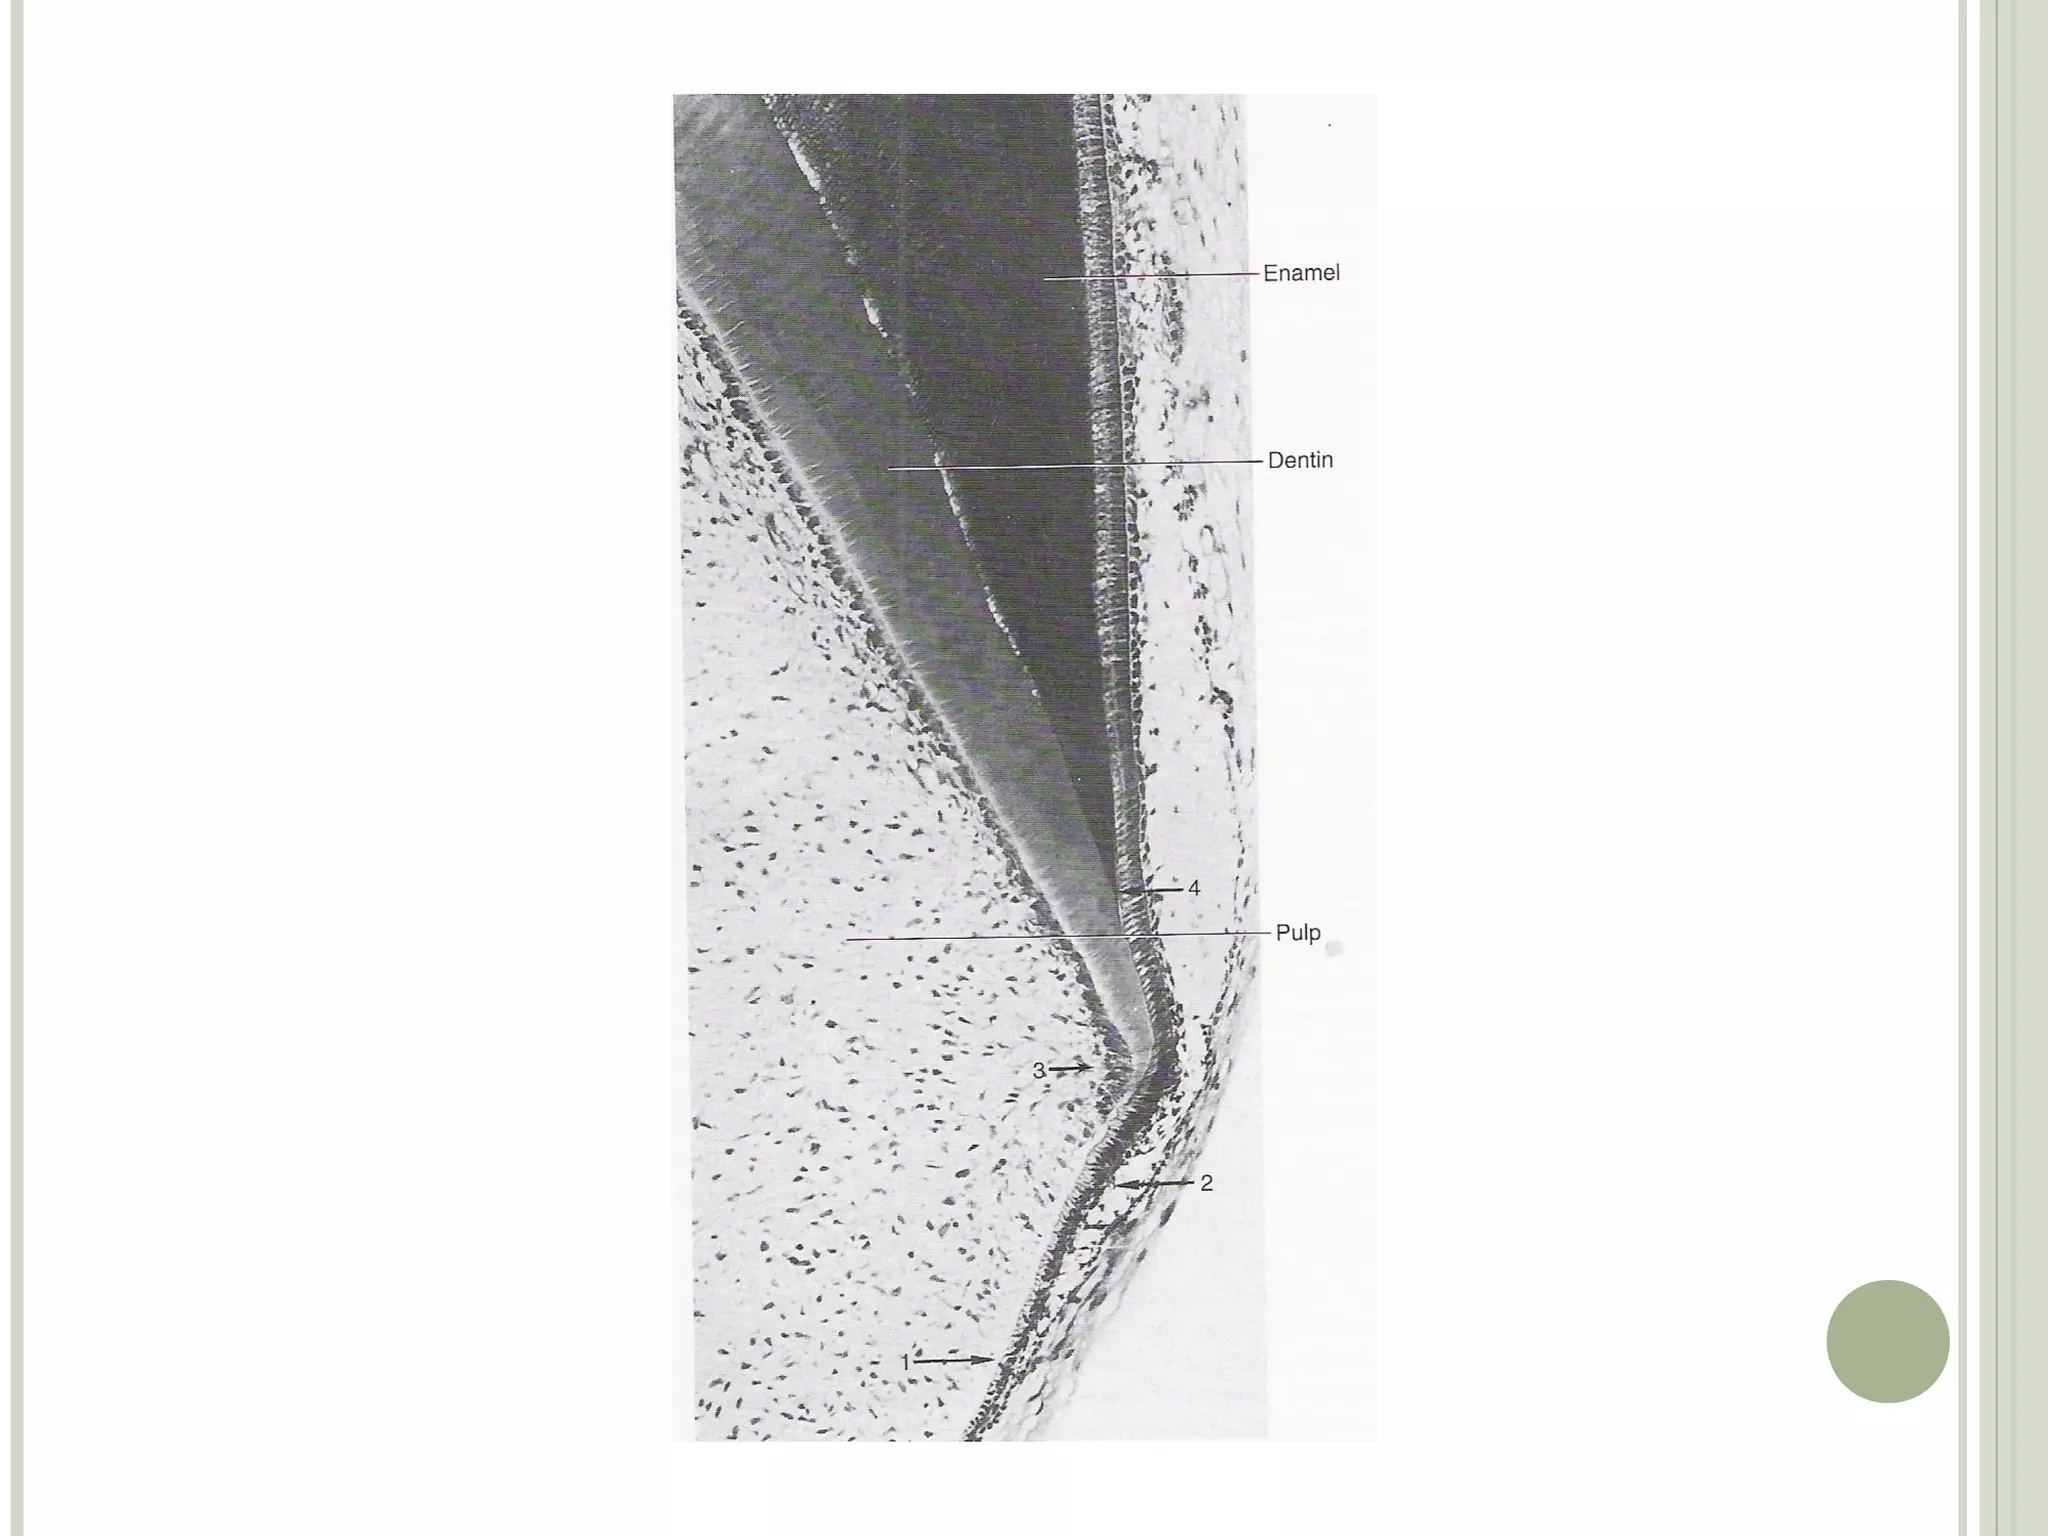

The root starts to develop after the crown is completed

 Epithelial cells of the inner and outer enamel epithelium

proliferate from the cervical loop to form two layers of

epithelium called Hertwigs root sheath

 The cells of the lengthening root sheath induce the

adjacent dental papilla cells to differentiate into

odontoblasts

 The newly formed odontoblasts then form the root

dentine

After dentine formation in root takes place, the epithelial

root sheath breaks down and its remnants migrate away

from the dentinal surface

They lie in the periodontal ligament and are called

epithelial rests of Malassez

The epithelial rests of Malassez are found the in the

periodontal ligament through out the life